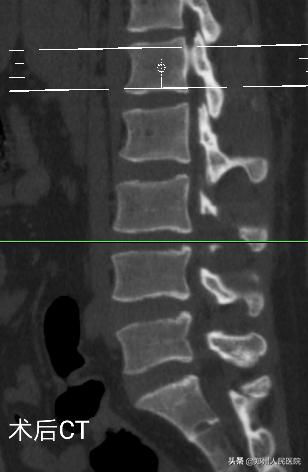

经过充分准备,对小葛实施的“单侧双通道UBE脊柱内镜术”如期举行。手术进行的十分顺利,经过一个半小时,手术成功。

在度过神经水肿期后,小葛的疼痛便消失了大半,由于手术对骨质的破坏很小,脊柱的稳定性得以最大程度的保留,手术后3天小葛就可以在腰部支具的辅助固定下行走活动,往日开朗的笑容又重新回到他的脸上。

为刘叔进行的“单侧双通道UBE脊柱内镜术”在不足两个小时后顺利结束,术中麻醉效果极佳,出血量只有数十毫升,清晰放大的视野下,突出的髓核及增厚的黄韧带完全摘除,骨性狭窄磨钻安全扩大减压,偶尔出现的小出血点也在射频刀头的控制下立即止血,轻松漂浮的神经根又重新出现了。